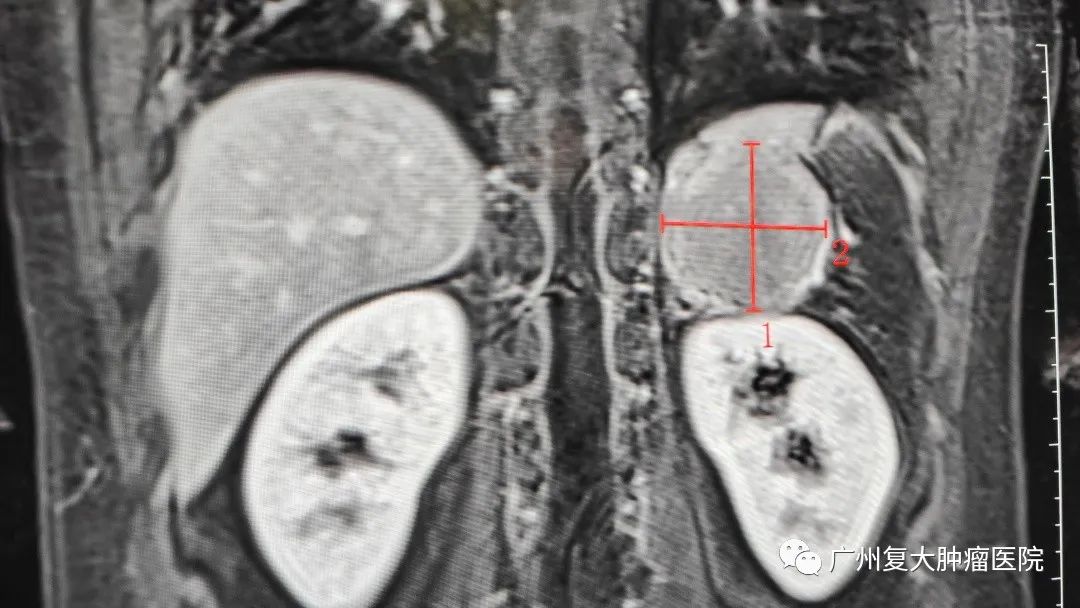

带着惴惴不安的心情,小伙子来到广州复大肿瘤医院就诊。入院后检查发现其彩超结果提示,左侧肾上腺区可见低回声肿物,边界清,内回声均匀,双肾血流灌注良好。为进一步诊断,小伙子又接受了上腹部MRI平扫+增强+DWI检查,脾脏缺如,脾脏术区可见大小约65×52×56mm团块灶,其内可见脾动静脉走行。

了解到患者几年前曾因车祸造成脾脏破裂,做过脾脏切除术,放射科李忠海主任结合影像结果及既往病史,认为该肿块并非肿瘤,而是副脾或残余脾脏代偿性增大。